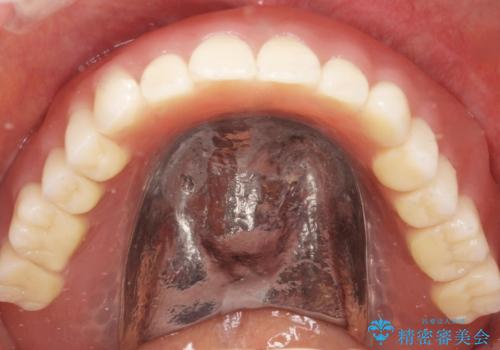

精査したところ、長年使用されていた入れ歯は劣化し、人工歯の脱離及び適合不良を認めました。

患者様のご希望により、上顎金属床義歯の新製を行いました。

適合を良くするため、咬座印象も行いました。